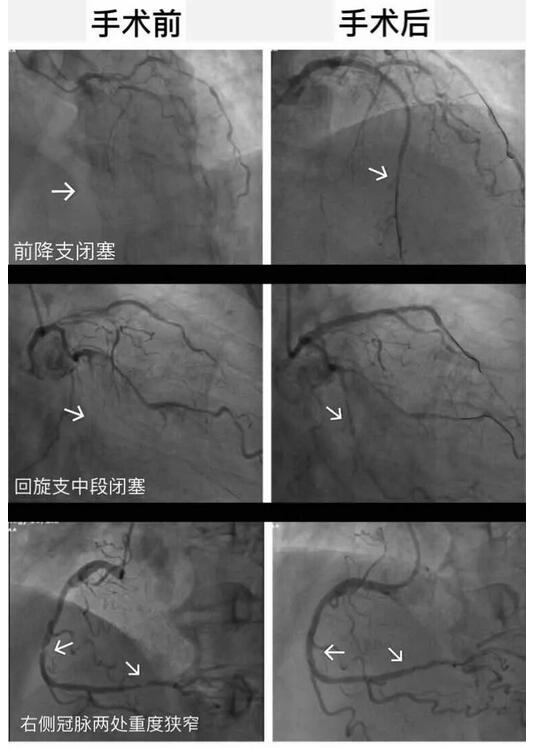

一次的手术并不能将贡大爷的病情完全缓解,按照术前血汗管内科主任李东旺的设想。2017年的7月份,贡大爷的第二次手术顺利完成,血管全部贯通,并完全恢复健康。术后恢复健康的贡大爷,望着窗外的景色脸上露出了往日的笑容。

△手术前后对比图